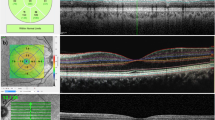

This is an observational case series with three patients with central retinal arterial occlusion (CRAO) and two patients with branch retinal arterial occlusion (BRAO). The macular/peripapillary RNFL thickness and the visual field were measured with Stratus optical coherence tomography (OCT) and Humphrey visual field analyzer, respectively, at least 1 year after the diagnosis of CRAO or BRAO.

The macular thickness, in particular the inner retinal layer, and the peripapillary RNFL thickness were reduced in patients with retinal arterial occlusion. The decrease in the macular and the peripapillary RNFL thickness corresponded to the sites of retinal arterial occlusion with diffuse and segmental thinning found in CRAO and BRAO, respectively. Visual field defects were found in the corresponding locations of macular and RNFL thinning, and closely correlated with the degree of the structural damage.

Structural damages in terms of reduction in the macular and peripapillary RNFL thickness were evident in patients with retinal arterial occlusion. A close structure–function correlation was found and a worse functional outcome is associated with a more extensive thinning of the macula and RNFL. OCT measurements of the macular/peripapillary RNFL thickness provide useful indicators to reflect the severity of the disease in retinal arterial occlusion and serve as a new paradigm to study and monitor the disease longitudinally.